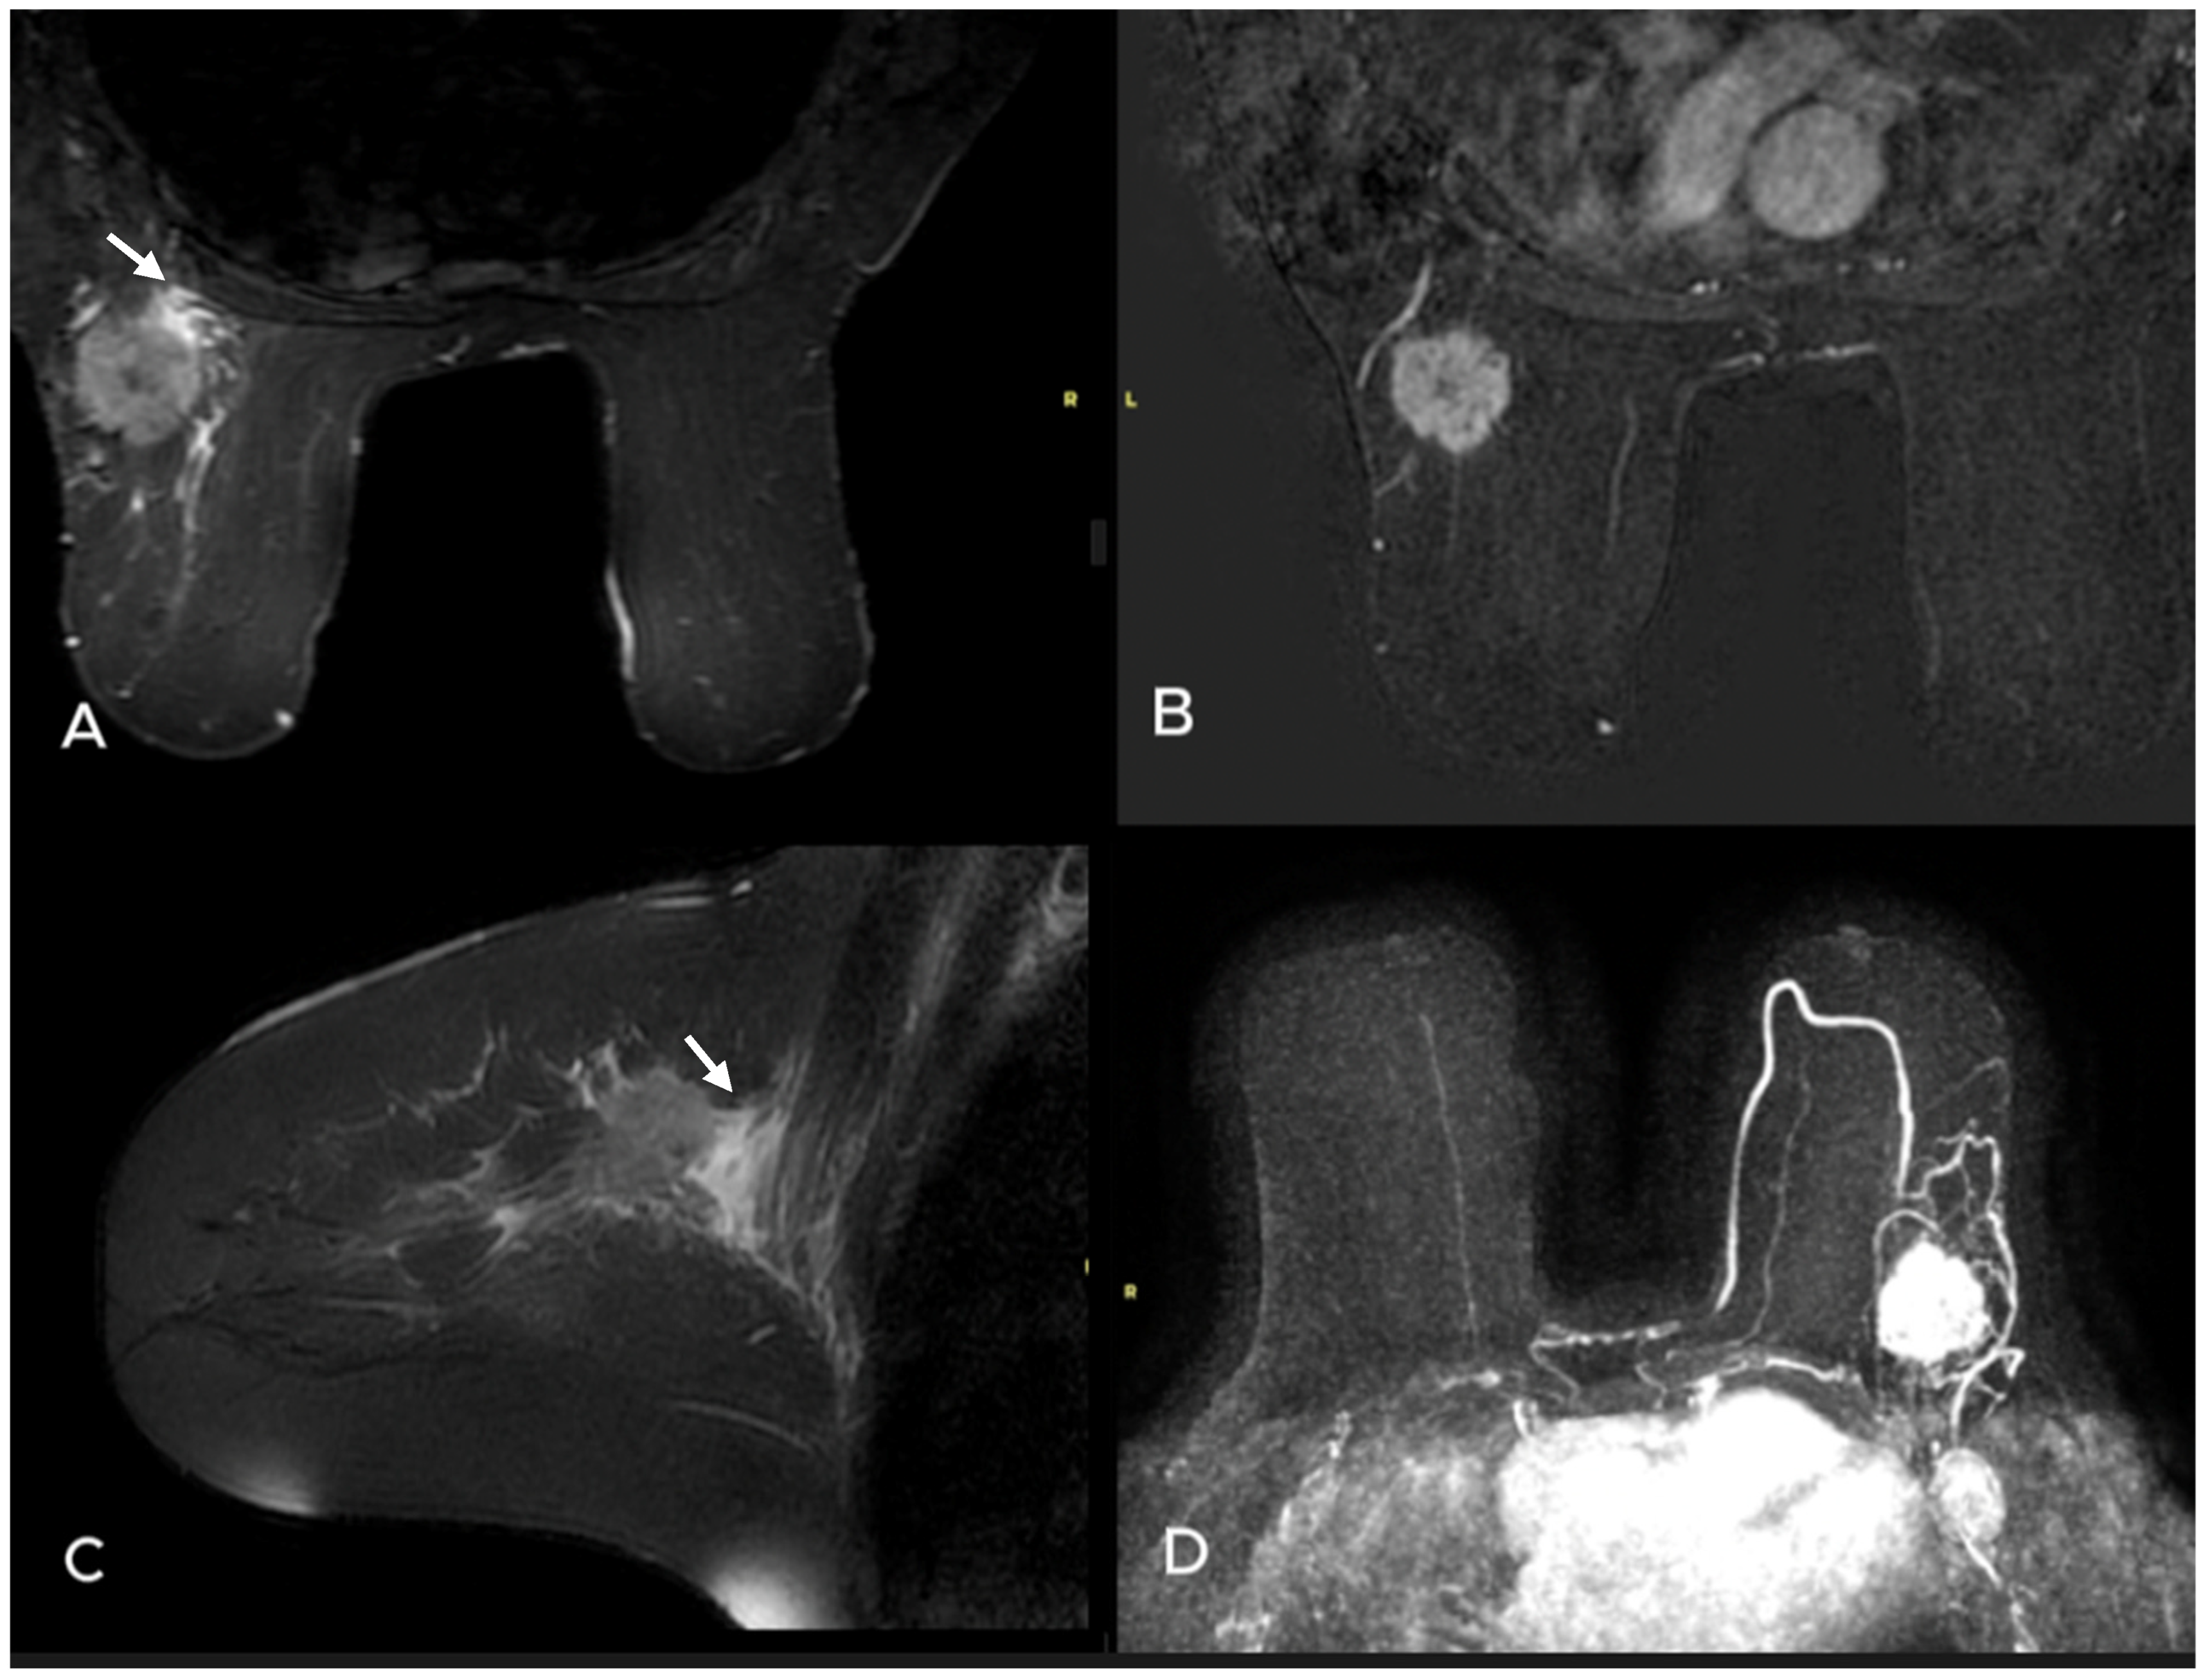

- Uematsu, T. Focal breast edema associated with malignancy on T2-weighted images of breast MRI: Peritumoral edema, prepectoral edema, and subcutaneous edema. Breast Cancer 2015, 22, 66–70. [Google Scholar] [CrossRef]

- Akdoğan Gemici, A.; Tokgoz Ozal, S.; Hocaoğlu, E.; Arslan, G.; Sen, E.; Altınay, S.; İnci, E. Relation of peritumoral, prepectoral and diffuse edema with histopathologic findings of breast cancer in preoperative 3T magnetic resonance imaging. J. Surg. Med. 2019, 3, 49–53. [Google Scholar]

| Presence of edema n (%) | 0.001 * | ||

| None | 17 (48.6) | 14 (15.9) | |

| Peritumoral edema | 14 (40.0) | 43 (48.9) | |

| Diffuse edema | 4 (11.4) | 31 (35.2) | |

| Presence of edema (none vs. perilesional-diffuse) | 3.19 | 1.71–5.95 | <0.001 | 2.46 | 1.11–5.48 | 0.027 |